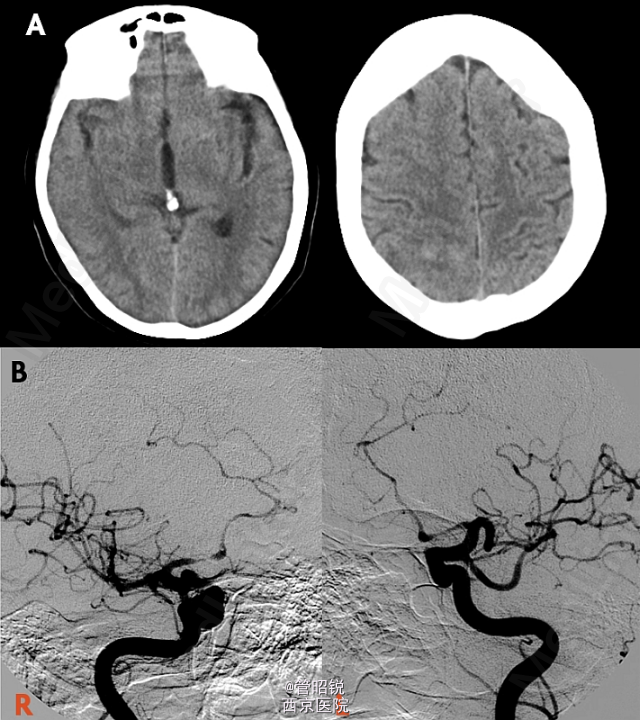

患者,男,71岁,急性头痛和腰痛。 慢性脊髓囊性蛛网膜炎是蛛网膜下腔出血的罕见并发症。此并发症被认为是由于溶血导致的蛛网 膜炎性反应,导致其纤维化和脊膜的继发性增厚,包括硬脑膜。纤维可形成囊腔包裹脑脊液,从而压迫脊髓,引起脊髓病和脊髓空洞积水征。一般保守治疗或者手术 CT显示轻微的脑室内出血,另外,在部分脑裂出可见模糊的高密度影,提示蛛网膜下腔出血。DSA双侧大脑前动脉狭窄。T1WI显示胸腰段脊髓腔内出血,定位在蛛网膜下。随访2年后,显示蛛网膜下的腔隙在脊髓表面形成扇贝样改变。随访3年腔隙仍然存在,以致脊髓表面继发性畸形。(来源于AJNR)